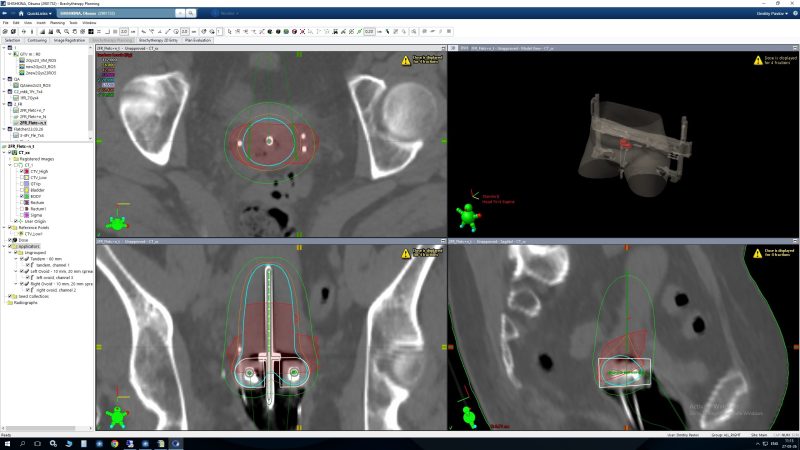

Дозиметрическое планирование только ICB Дозиметрическое планирование ICB/ISB

• Подавляющее большинство пациенток с гинекологическими заболеваниями получают внутриполостную брахитерапию (ICB), однако гибридная брахитерапия, включающая внутриполостную (ICB) и внутритканевую (ISB) компоненты, рекомендуется пациенткам, у которых применение ICB приводит к неоптимальному распределению дозы. ISB следует рассматривать у пациентов с обширным поражением параметрия, крупными первичными опухолями, а также при узком или дистальном поражении влагалища.

Данные исследований демонстрируют преимущество в локальном контроле у пациенток с крупными опухолями шейки матки, получающих гибридную ICB/ISB, по сравнению с применением только ICB.